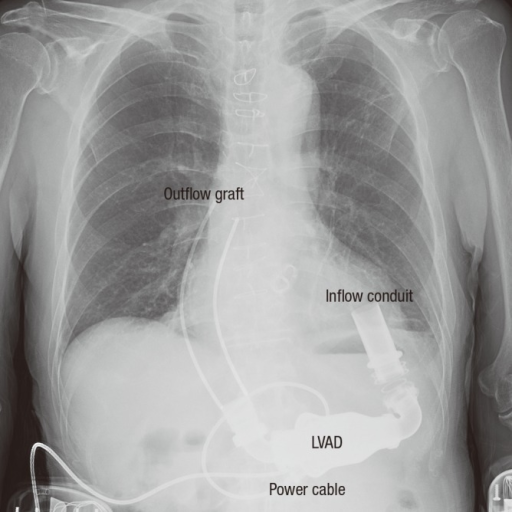

Interpreting lines and tubes on radiographs | The BMJ

Chest X-ray after LVAD implantation. (The illustration | Open-i